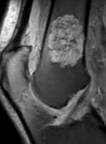

Stanford Musculoskeletal MRI atlas

MSK anatomy atlas, educational talks, and cases. ~1.7M pageviews.